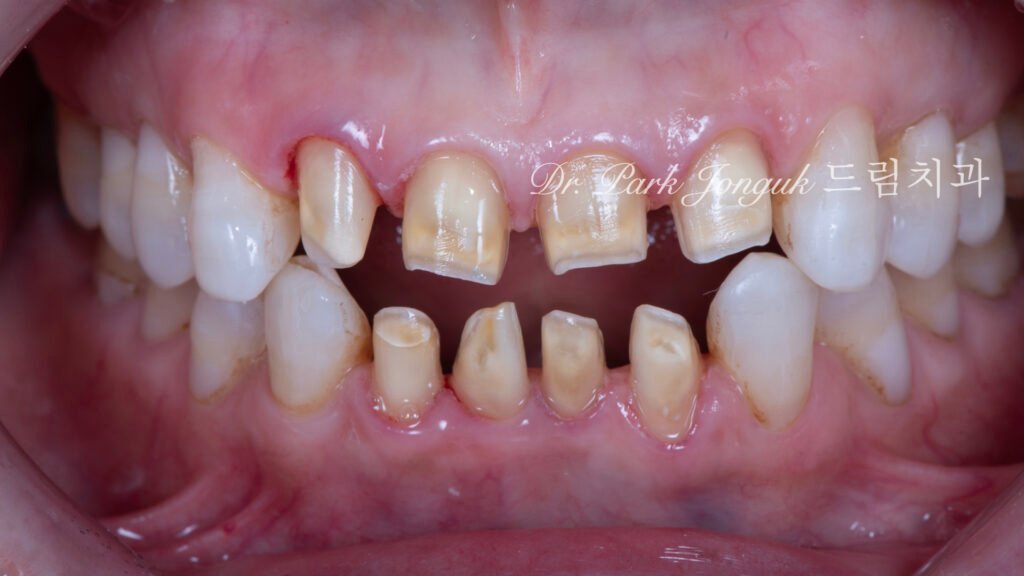

상악 평가

사진 1은 치료 전 상악(Maxillary arch) 상태입니다.

탁한 색상(Dull color): 불투명하고 생기 없는 색조를 보입니다.

평면적 형태(Flat morphology): 자연치아의 입체적 특성이 결여되어 있습니다.

파절 확인: 중절치에 파절이 관찰됩니다.

하악 평가

사진 2는 치료 전 하악(Mandibular arch) 상태입니다.

상악과 유사한 문제: 아래 치아도 위 치아와 마찬가지로 탁하고 어색한 색조와 형태를 보입니다.

상하악 통합 재시술 필요성: 위아래 모두 재시술이 필요한 상태로, 상하악을 통합적으로 재시술하여 조화로운 결과를 달성하기로 결정했습니다.

충격적 발견: 라미네이트가 아닌 크라운 수준의 삭제

초진 검사에서 놀라운 사실이 발견되었습니다.

과도한 삭제의 확인

검사해 보니 말이 라미네이트지 거의 크라운입니다. 촉진(Palpation), 방사선 검사(Radiographic examination), 시각적 평가를 통해 치아 삭제량이 라미네이트 기준(0.3-0.5mm)을 훨씬 초과하는 것으로 확인되었습니다.